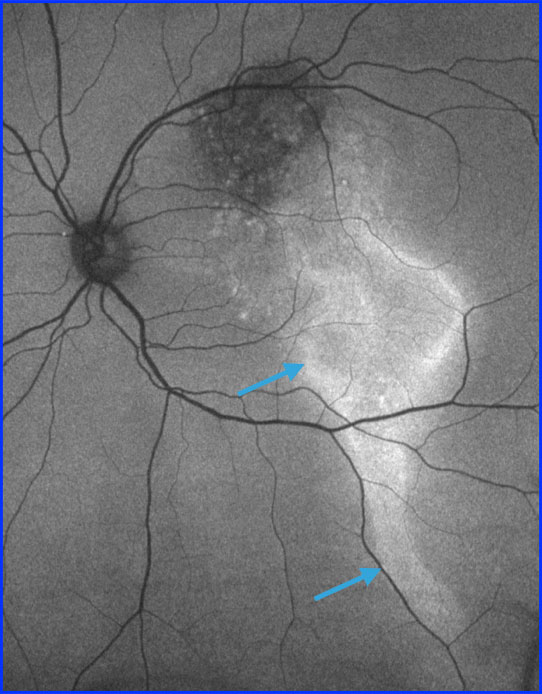

On autofluorescence the appearance of a gutter-like change (arrows) can be noted due to chronic fluid exudation in a gravity-dependent manner.